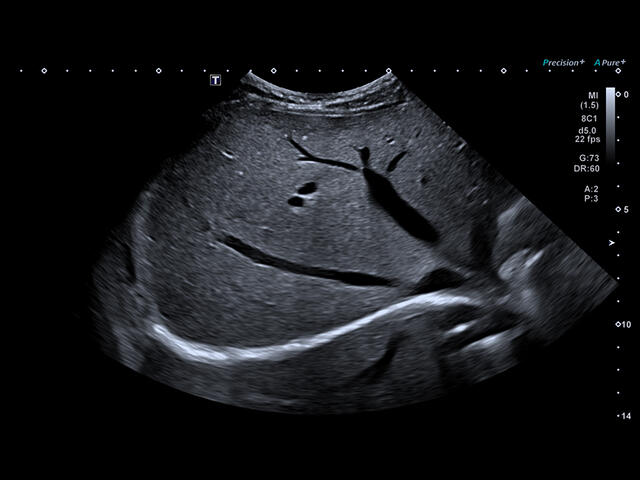

- Fly Thru. Виртуальная эндосонография обеспечивает построение трехмерной модели полостей, протоков и сосудов в реальном времени, облегчает организацию инвазивных процедур и динамических исследований. Посредством Fly Thru можно установить шунты и стенты, проводить точные оперативные вмешательства.